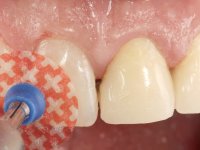

Durante esse período foi também removida a férula dos dentes 1.3, 1.2 e 1.1 no sentido de avaliar a sua estabilidade. Esta remoção foi feita com muito cuidado para não danificar a superfície vestibular dos dentes. Foram utilizados discos de polimento de forma sequencial e taças de borracha. Após a repetição de testes de vitalidade verificou-se a necrose do dente 1.1, tendo sido realizado o necessário tratamento endodôntico. A impressão definitiva foi feita com a técnica de dupla mistura e o caolino utilizado como afastamento gengival. A ponte provisória foi mais uma vez rebasada. No laboratório, utilizando a tecnologia CAD-CAM, foi feita uma infraestrutura em Zr e posteriormente revestida com cerâmica. Durante este processo sentimos a necessidade de acrescentar resina composta por mesial do dente 2.3 com o objetivo de manter os diâmetros mesio-distais simétricos aos dentes do 1.1 e 1.2. Nesse sentido foi confecionada uma chave de silicone transparente que seria utilizada em boca para orientar esse acrescento. Na porção mesial da superfície palatina do dente 2.1 da ponte foi feita uma pequena cavidade que seria utilizada para colocar uma pequena férula de arame com o objetivo de assegurar a eventual abertura de um diastema. Em boca foi realizado um isolamento relativo e feito o acrescento de resina composta no 2.3 com a ajuda da chave de silicone. A ponte foi cimentada definitivamente com cimento de ionómero de vidro reforçado com resina. Finalmente foi colado uma pequena porção de arame entre a ponte e o dente 1.1.